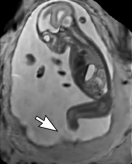

During image acquisition the fetus is not sedated and moves freely as well as the mother breathes normally. As a result, movements are likely to corrupt the scans, hiding pathology and causing overlap between different anatomical regions. In order to limit these artifacts, fast scanning sequences such as ssFSE [10] allow for the rapid acquisition of single slices at high in-plane resolution in a large field of view and good tissue contrast of the uterus. However, when acquiring a 3D volume through a stack of slices, inter-slice artifacts in the out-of-plane views are highly likely. Consequently, this restricts reliable diagnostics to individual slices in the current clinical practice. Fig. 1 depicts a typical example of motion related artifacts in a fetal single-shot fast spin echo (ssFSE) scan. The observed motion (c.f. Fig. 1 b & c) is of unpredictable nature and consists of a combination of maternal respiration movements, fetal movements and bowel movements.

Reconstruction of Fetal Organs: Exemplary PVR and SVR reconstructions under motion introduced by kicking of the fetus are shown in Fig. 11. PVR reconstruction results show an improved visual appearance and less blurring in the region with severe motion artifacts (arrow). An example of a challenging clinical case with a kidney malformation in one of twin fetuses, is shown in Fig. 8. Our clinical partners confirmed that such complications are easier to examine and to quantify after PVR-based reconstruction.